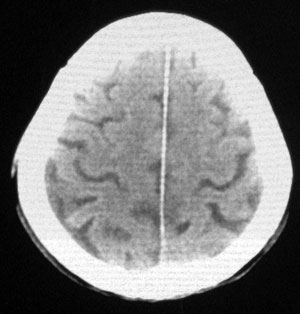

男性,65岁,头疼。 看看这大脑镰,ct值约83hu .

楼主的意思是让我们看大脑镰串珠样钙化,虽然ct值83hu ,也应该是钙化.(循环渐进).

男性,65岁,头疼。 看看这大脑镰,ct值约83hu .考虑蛛血,应该结合临床

感觉应该是生理性钙化

是生理性钙化

头痛与大脑镰钙化应该关系不大。

没有问题的!老年人!头痛的原因很多!大脑镰的钙化这样年龄的病人可以不提示!

大脑镰钙化,应该没有疑问吧